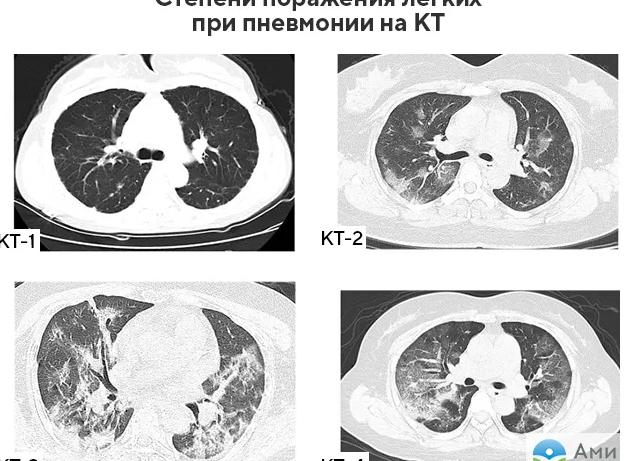

• все виды пневмонии;